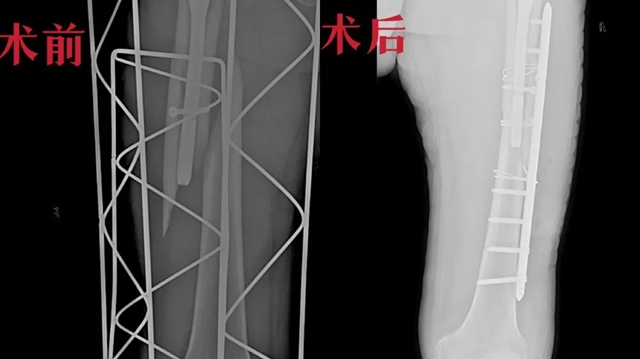

第二次术前术后对比图

“右股骨骨折切开复位钢板内固定术”